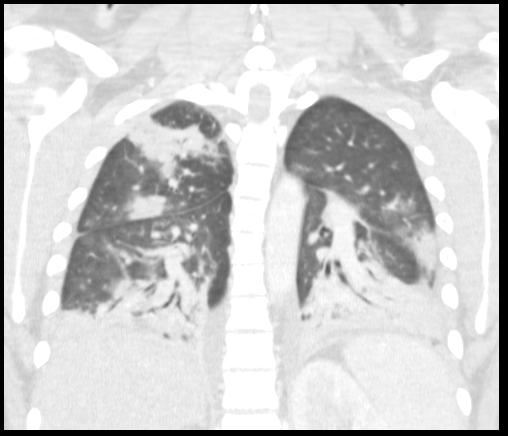

On initial evaluation, T 37.6 ᵒC, BP 93/60 mmHg, HR 146/min, SpO2 98% on 2 L of nasal cannula oxygen. He is a well-nourished young male in acute distress. He had bilateral tonsilar enlargement, swollen uvula with bilateral anterior cervical lymphadenopathy. His cardiac exam revealed tachycardia, regular rhythm with no murmurs. His lung exam revealed bilateral air entry with no added sounds. His abdomen was soft. No skin rashes were noted and his neurological examination was non-focal. Initial laboratory investigations showed acute kidney injury, lactic acidosis, leukocytosis, lymphopenia and thrombocytopenia. CXR was normal. EBV serology, throat culture, respiratory virus panel and HIV and cocci serology were negative. Blood cultures were drawn and the patient was volume resuscitated. A working diagnosis of sepsis secondary to EBV pharyngitis was made. On day 1 of hospital stay, he reported cough, CT chest showed multifocal pneumonia suggesting hematogenous spread of infection. Given the septic embolic presentation and sore throat, Lemierre’s disease was considered. He was started on broad spectrum antibiotics. CT scan of the neck showed a partially occlusive thrombus in the left internal jugular vein. Blood culture eventually grew F. necrophorum and was sensitive to amphicillin-sulbactam and meropenem. Antibiotic therapy was de-escalated to amphicillin-sulbactam. He remained febrile for five days even after the start of antibiotic therapy. Repeat blood cultures were negative. The patient was discharged home on 4 weeks of IV antibiotic therapy. On follow up after 4 weeks, he was doing well and antibiotic was switched to oral to complete 6 weeks of therapy.